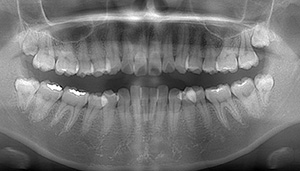

- 抜歯前写真(レントゲン、CT等)

左下の親知らず周囲歯肉が腫れていました。

また、手前の歯との間で虫歯もできていました。